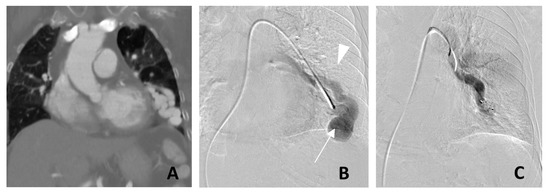

2. Radiological Diagnosis